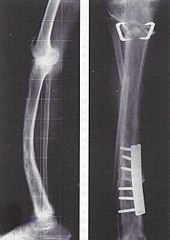

Monostotische Osteodystrophia deformans einer Tibia mit Antekurvation und Varusstellung, 74-jährige Patientin. Die Varität wurde durch eine valgisierende Pendelosteotomie im Schienbeinkopf, die Antekurvation durch eine Keilresektion im unteren Tibiadrittel korrigiert. Dazu musste die Fibula im oberen und unteren Drittel osteotomiert werden. Die Osteotomien wurden fest, die Patientin beschwerdefrei. Ein Jahr nach dem Eingriff verstarb die Frau an einem Nierenkarzinom. | eigenes Archiv (abgedruckt in: Rüdiger Döhler: Lexikon Orthopädische Chirurgie, Springer 2003, S. 145) | Mehlauge | Datei:Tibiaumstellung bei Paget.jpg |